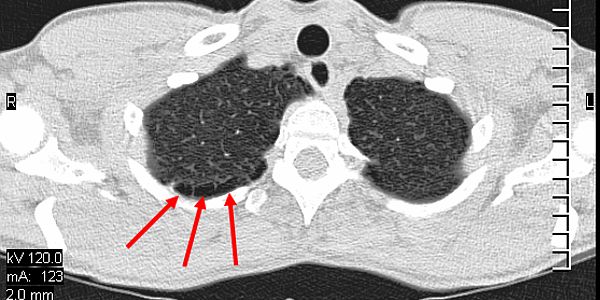

Air Trapping Ausschnitt Quiz Bbe

COPD

Für uns Taucher ist die Lunge natürlich mit das wichtigste Organ. Daher sollte mit der ersten Tauchtauglichkeit die Lunge eines Tauchers eingehend überprüft werden. ... weiterlesen

Beispiel Bullae Ec

Pulmonales Barotrauma

Das Hyperbare Medical Center in Sharm el Sheikh hat über die Jahre Hunderte von Tauchunfällen behandelt; ein Pulmonales Barotrauma ... weiterlesen